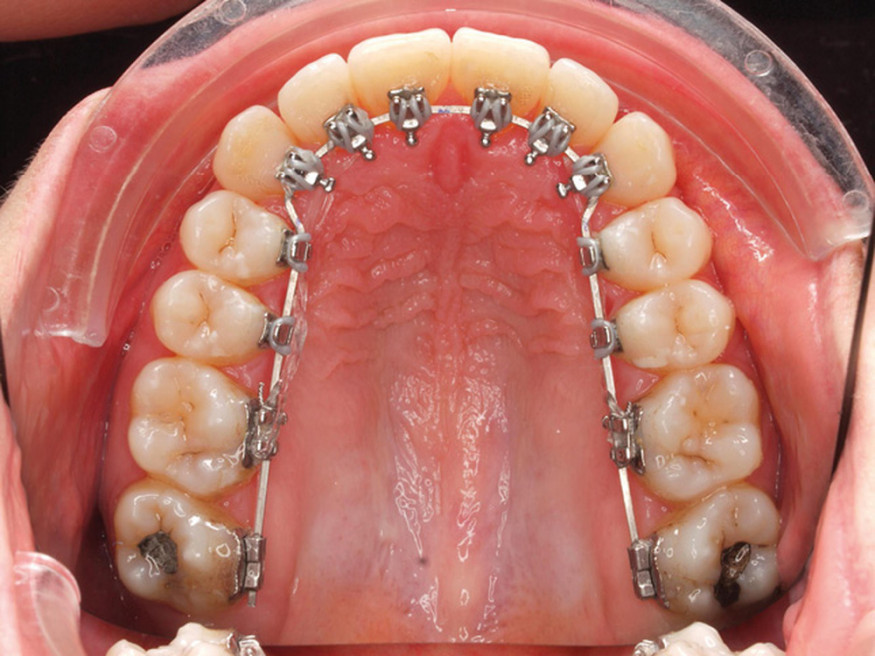

1. Appareil lingual posé en bouche. ✔ Les principes de l’orthodontie linguale sont les mêmes que ceux de l’orthodontie vestibulaire : l’appareillage lingual est constitué d’attaches (brackets), qui sont collées sur les faces linguales ou palatines de chaque dent et reliées par un arc dentaire. Ce fil métallique plié sera changé régulièrement de façon à déplacer les dents en exerçant une pression légère. La principale différence avec l’orthodontie vestibulaire réside dans l’individualisation précise de chaque attache pour qu’elle s’adapte à l’anatomie spécifique des faces linguales des dents. ✔ Sur le plan mécanique, les attaches linguales déplacent donc les dents en les tirant ou les poussant comme le font les brackets externes vestibulaires : elles permettent donc les mêmes résultats. |